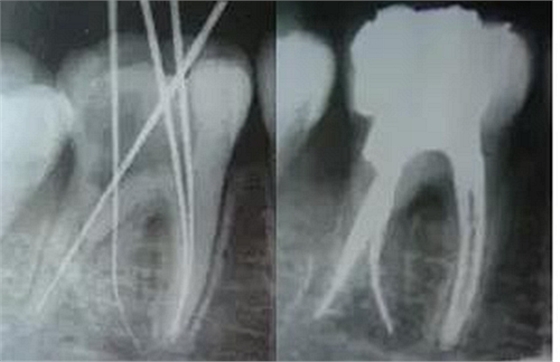

5、確定工作長(zhǎng)度:15號(hào)K銼進(jìn)入時(shí)最好配合根測(cè)儀;術(shù)前,術(shù)中,術(shù)后都要拍X—RAY。

最后來玩一個(gè)根管治療質(zhì)量的評(píng)估——下圖是武大彭彬教授的一個(gè)病例,仔細(xì)觀察可以挑出一點(diǎn)問題,但問題事出有因!看看你的“眼力”如何——問題在那里?教授的專業(yè)水平是不用懷疑的,那么事出的原因可能是什么?

問題答案:這個(gè)病例的問題主要反應(yīng)在開髓的洞形修整,注意觀察該牙X-RAY的左側(cè)洞壁,如果常規(guī)情況制備成這樣是由于裂鉆破壞了洞壁和洞底所形成的臺(tái)階。如果評(píng)估根管治療的質(zhì)量那是要扣分的!但這個(gè)病例仔細(xì)觀察洞壁形態(tài)就可以看出:該病例屬于再治療的病例,因此還是屬于一個(gè)理想的病例。